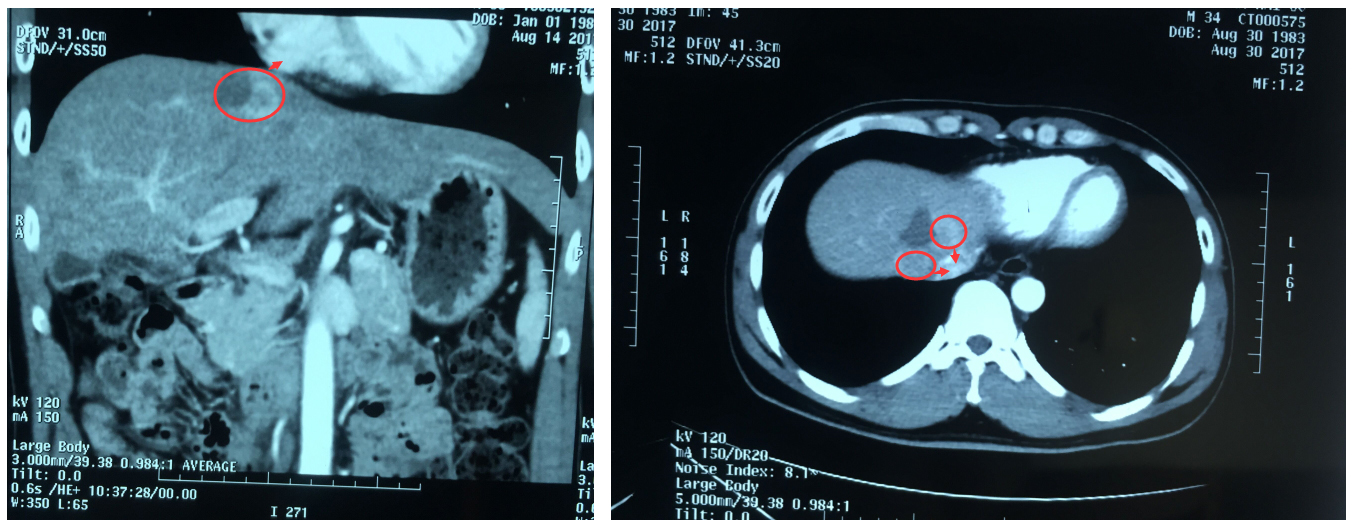

更让人心痛的是,经检查,他的肝脏肿瘤位置非常特殊:不仅位于膈脚下腔静脉旁,而且距离心脏只有1.5cm,不宜再行传统外科手术。常规肿瘤消融术又不足以彻底消灭肿瘤,那该怎么办呢?

▲患者肝脏肿瘤距离心脏1.5cm,位于膈脚下腔静脉旁